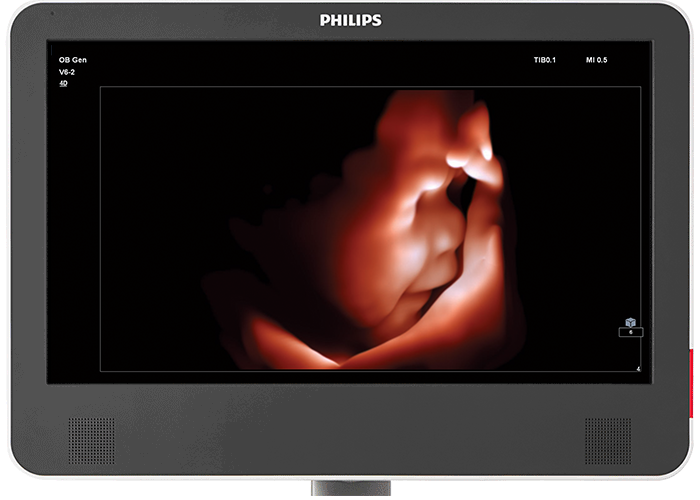

Tehnologia TrueVue şi TouchVue

Funcţia Philips TrueVue cu sursă virtuală de lumină reprezintă o metodă brevetată de imagistică ultrasonografică în tehnologia 3D, permiţând obţinerea de proiecţii tridimensionale realiste. Operatorul aparatului poate mişca în orice mod sursa de lumină, în cadrul volumului imaginii 3D. Folosind interfaţa interactivă TouchVue, utilizatorii ecografului pot, cu ajutorul panoului tactil, să controleze atât rotirea volumului, cât şi amplasarea sursei interne de lumină direct pe imaginea 3D obţinută cu ajutorul funcţiei TrueVue.